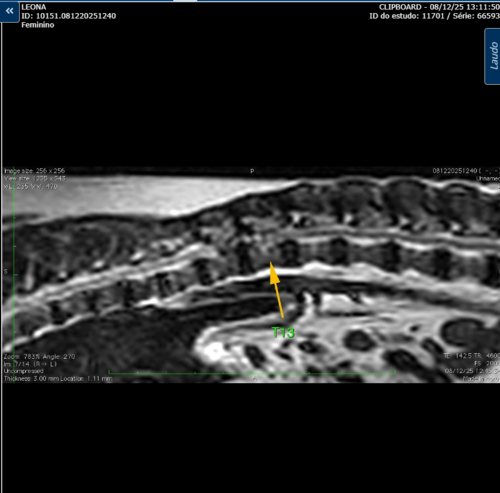

Mesmo com todos os cuidados possíveis ela vai precisar passar por uma cirurgia pois se criou (pelo que nos foi explicado pelo veterinario) uma ‘’hernia de disco'', deixando ela sem os movimentos das patinhas de trás.

Segue os laudos para comprovação